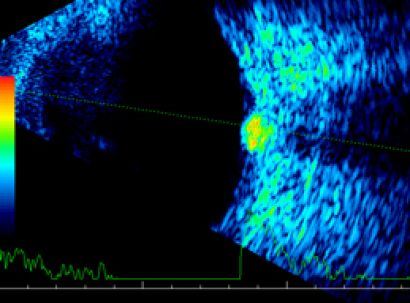

![]() |

| Пролиферативная диабетическая ретинопатия | Осложненная катаракта |